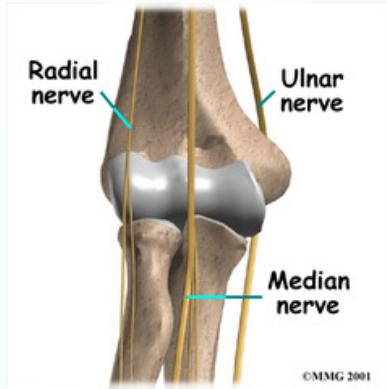

Nerve injury: Median, Radial

- Test: Oppose thumb with little finger

- Test: Flex/extend fingers/wrist